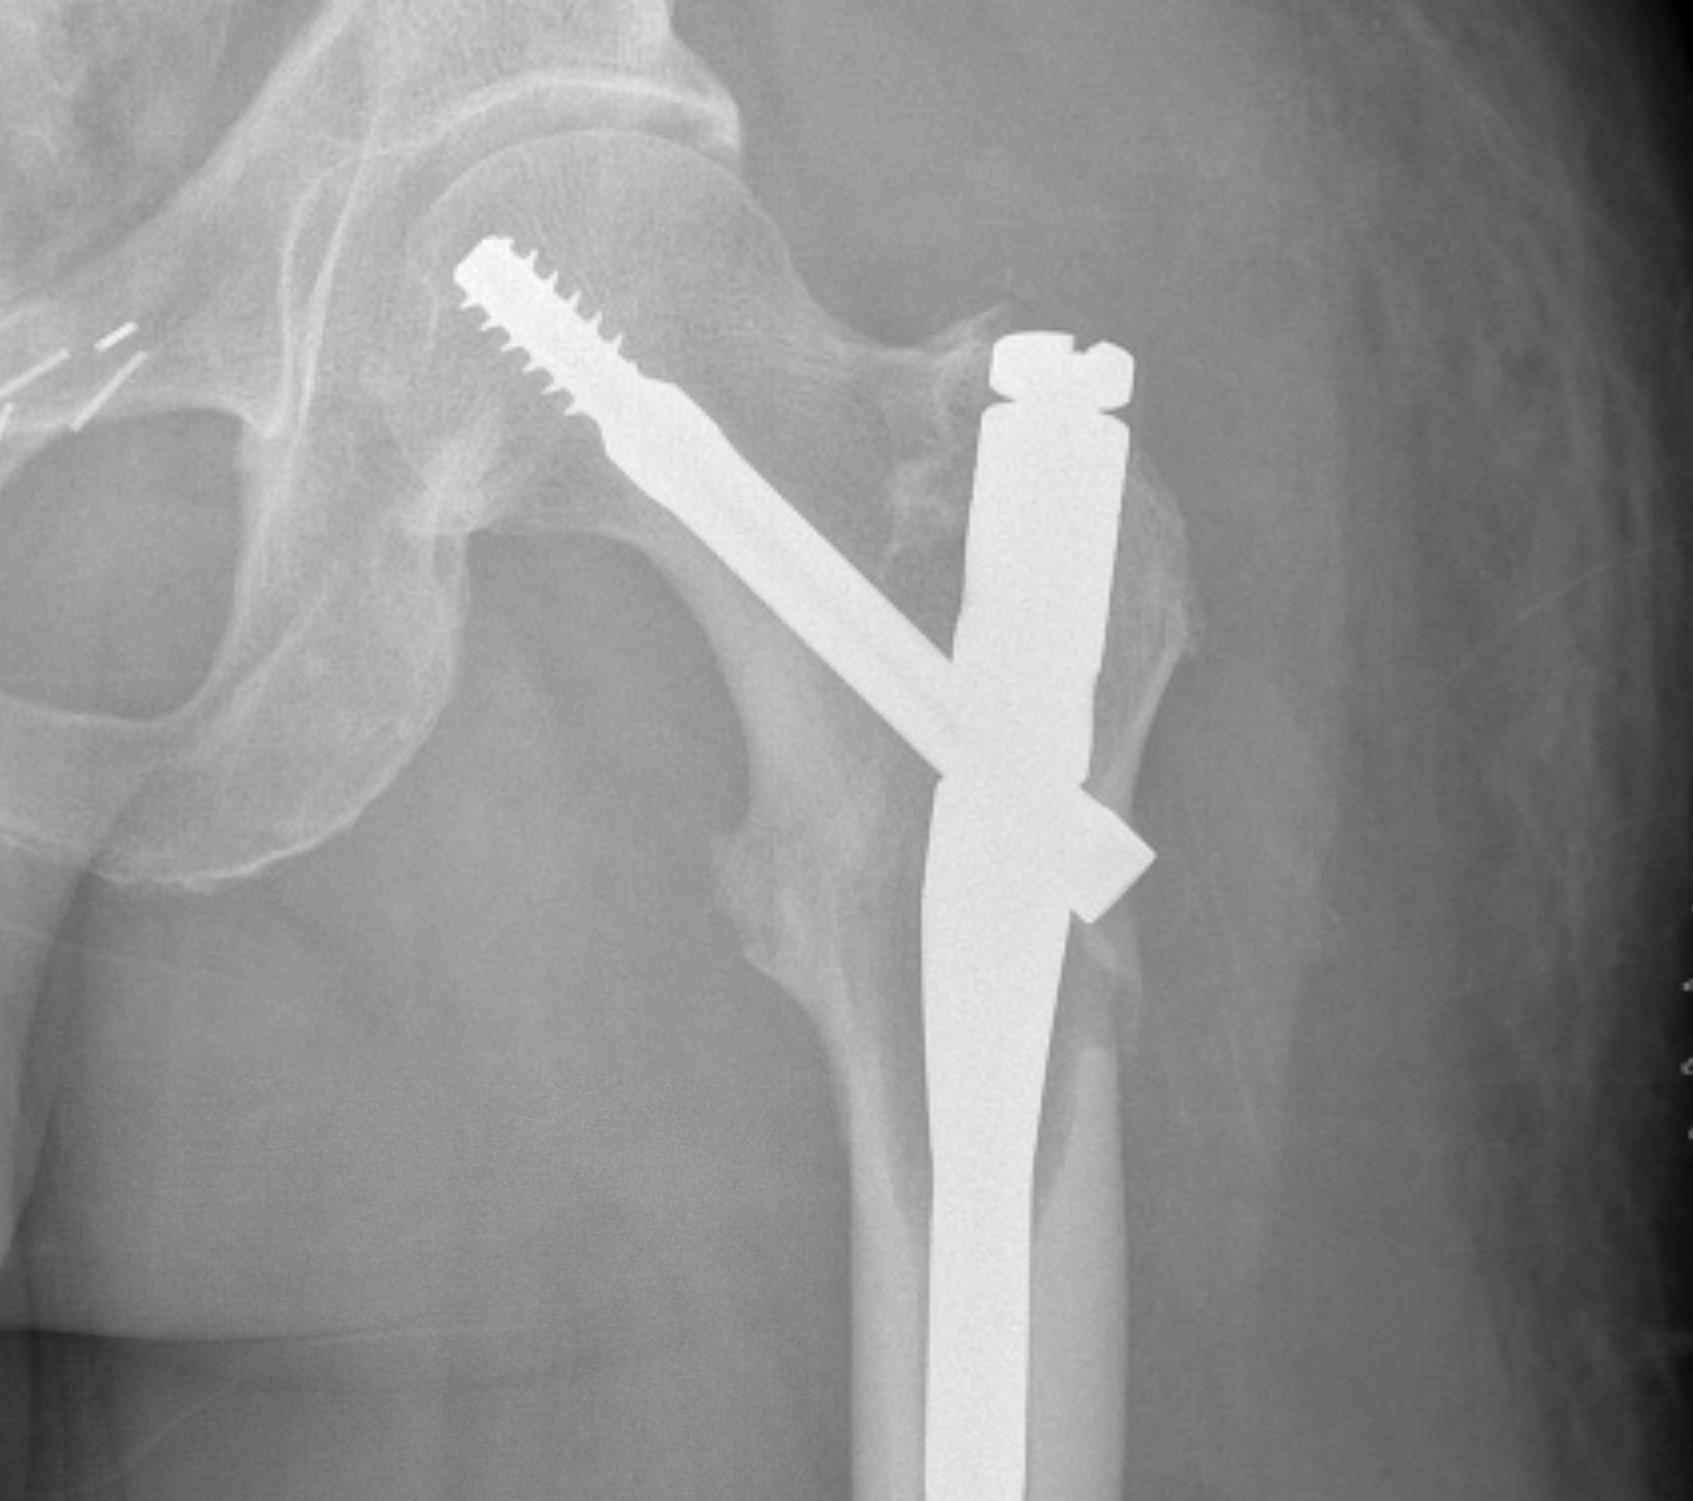

Plate versus IM nail

Meynard et al Orthop Traumatol Surg Res 2020

- 309 cases proximal femoral metastasis

- plate versus IMN versus arthroplasty

- no difference in functional outcome

- increased complications with plating